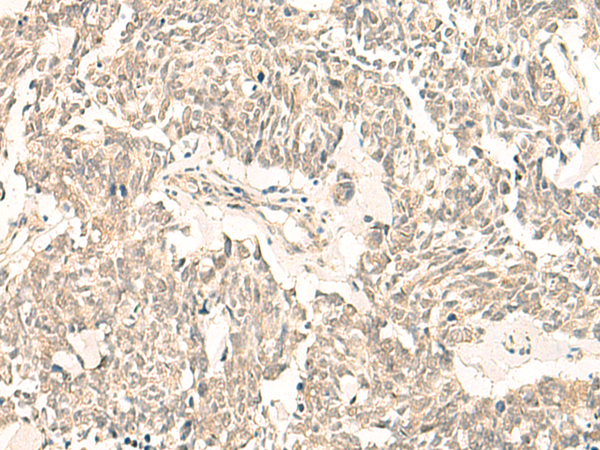

分类: 科研抗体货号: P02993别名: F5F8D; SDNSF; F5F8D2; LMAN1IP应用: IHC反应种属: Human, Mouse, Rat